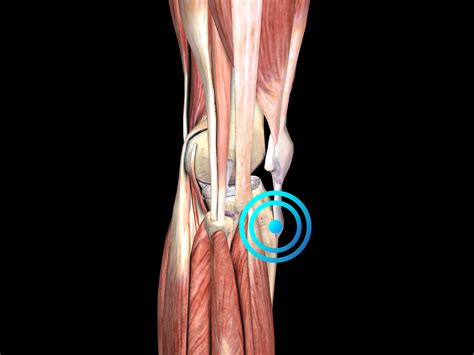

Osgood-Schlatter disease is a condition that frequently affects active adolescents during their growth spurts, leading to painful inflammation at the top of the shinbone where the patellar tendon attaches. While the vast majority of cases resolve on their own with rest, ice, and physical therapy, there are rare instances where the symptoms persist into adulthood or cause significant structural deformity. In these specific, chronic cases, patients and medical professionals may begin to discuss an Osgood Schlatter operation as a final option to restore function and alleviate chronic discomfort. Understanding when this procedure is necessary, what it entails, and the recovery process is vital for those who have exhausted conservative treatment methods.

Most teenagers outgrow the condition once their bones fully mature and the growth plates close. However, when a patient reaches skeletal maturity and continues to experience pain, it is often due to the formation of a prominent, ossified (bony) bump or a loose fragment of bone that remains trapped within the patellar tendon. An Osgood Schlatter operation is not a first-line treatment; it is strictly reserved for patients who have finished growing and still suffer from:

The goal of the surgery is generally to excise the painful ossicle—a small piece of bone that failed to fuse with the main tibia—and to clean up any damaged or scarred tissue within the tendon. By removing this focus of inflammation, the surgeon helps the patient regain a pain-free range of motion.

The surgical procedure is typically performed under general or regional anesthesia. The surgeon makes a small incision over the tibial tubercle, the area where the pain is localized. Once the area is exposed, the surgeon carefully identifies the ossicle or the prominent bony protrusion. Using specialized instruments, they remove the bony fragment while being extremely cautious not to damage the attachment point of the patellar tendon itself, as this is critical for knee extension.